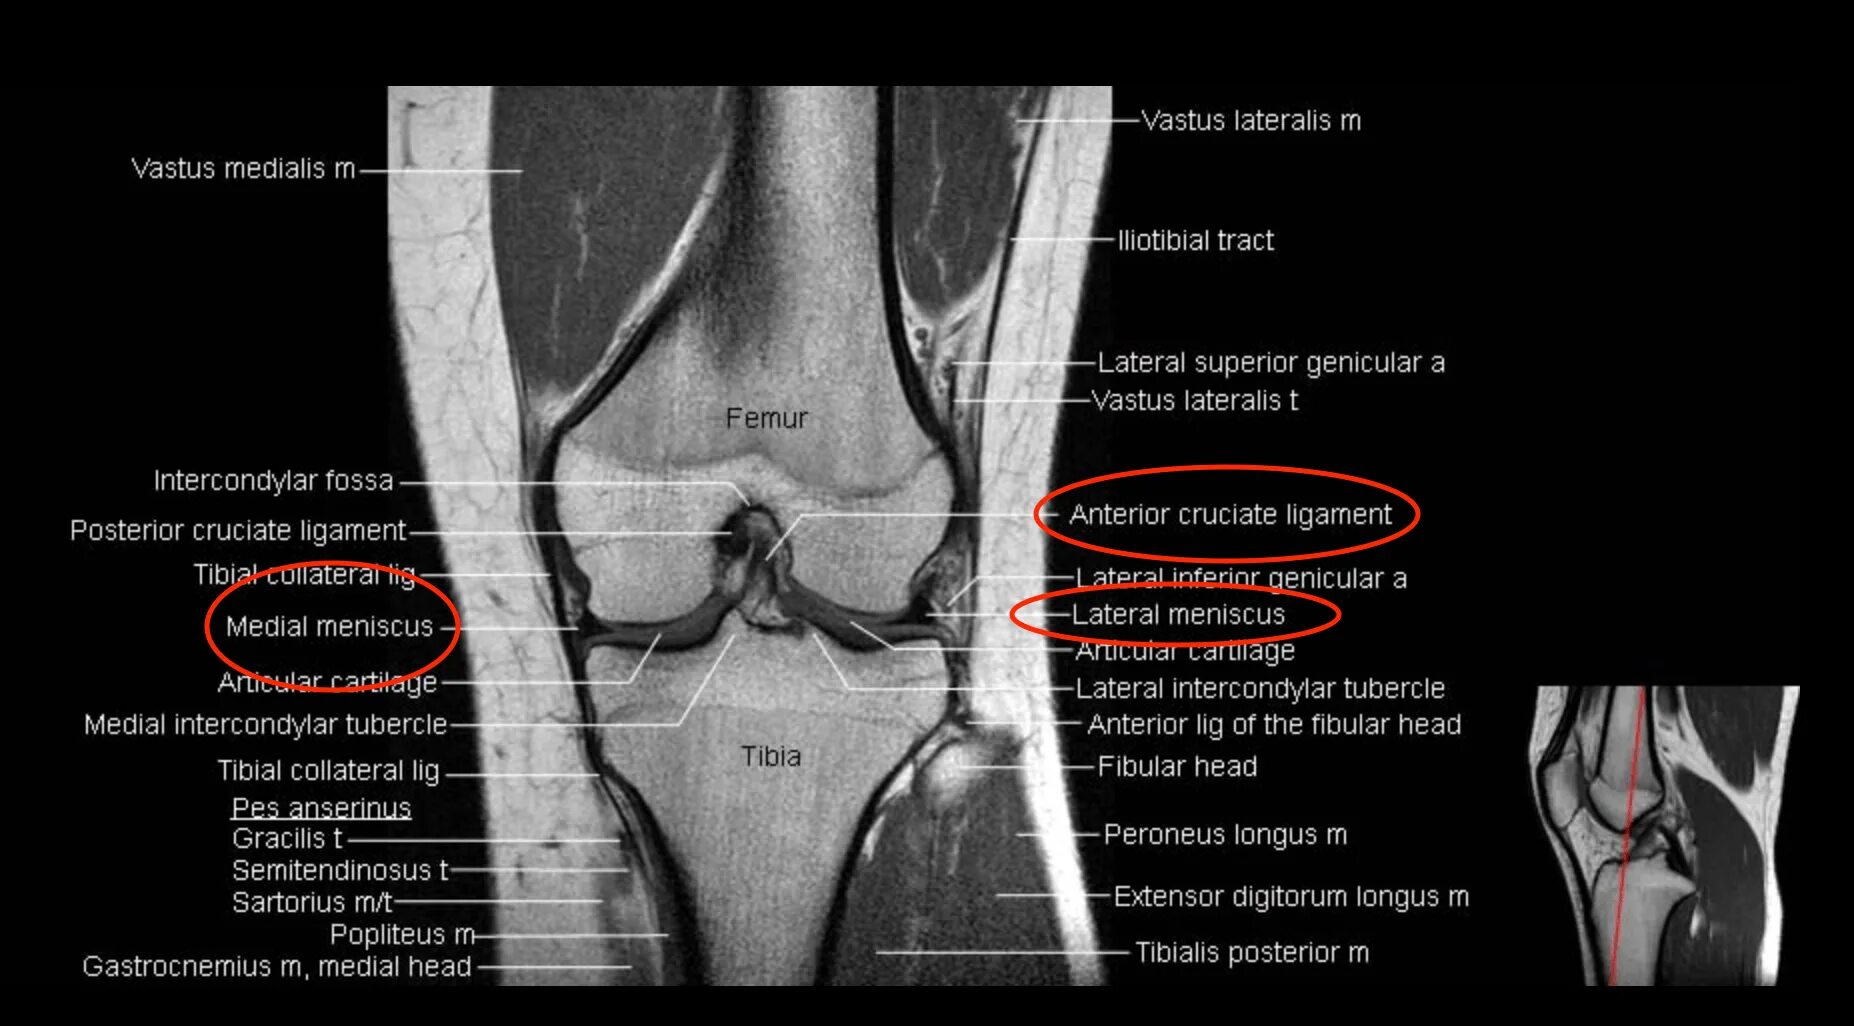

Мрт коленного сустава одежда